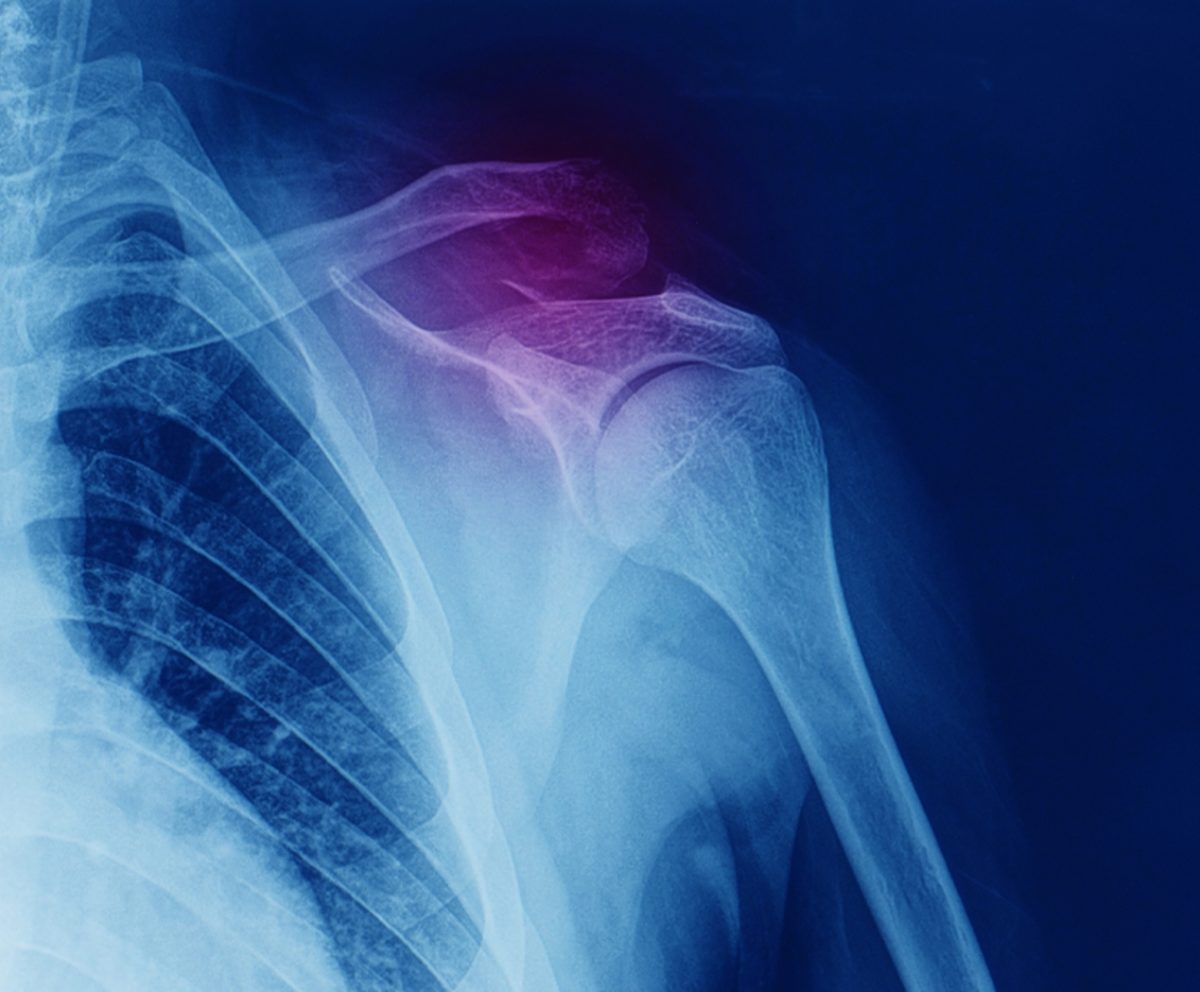

Οστεοπορωτικά κατάγματα: Η «μάστιγα» του 21ου αιώνα

Η οστεοπόρωση, γνωρίζουμε καλά τα τελευταία χρόνια, ότι είναι η οστική νόσος που χαρακτηρίζεται από μειωμένη οστική πυκνότητα και ποιότητα, πράγμα που οδηγεί στην ευθραυστότητα των οστών και σε αυτό που ονομάζουμε οστεοπορωτικό κάταγμα ή κάταγμα χαμηλής βίας.

Οστεοπορωτικό κάταγμα μπορεί να συμβεί σε οποιοδήποτε μέρος του σκελετού αλλά τα συνηθέστερα οστεοπορωτικά κατάγματα είναι τα κατάγματα της σπονδυλικής στήλης, τα κατάγματα του ισχίου και τέλος τα κατάγματα του καρπού. Από αυτά, τα κατάγματα της σπονδυλικής στήλης αντιμετωπίζονται κυρίως συντηρητικά με κατάκλιση αρχικά και στη συνέχεια προοδευτική κινητοποίηση με κηδεμόνες ή ζώνες αλλά αφήνουν δυστυχώς τις περισσότερες φορές προβλήματα, με αποτέλεσμα την κακή ποιότητα ζωής.